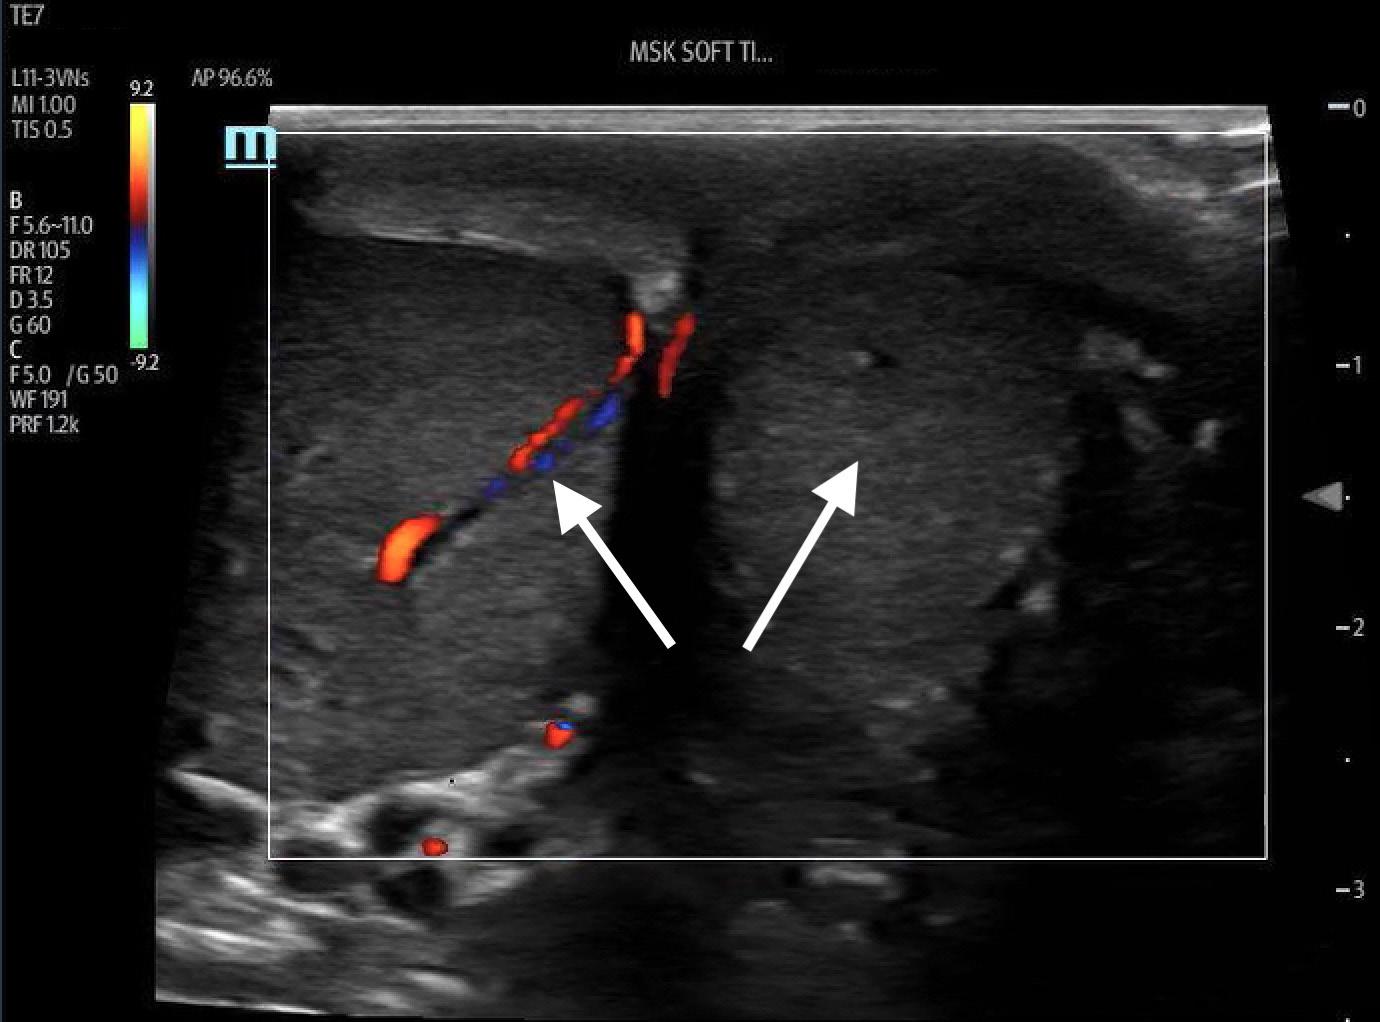

Ultrasound-guided PTN blocks were performed using the same technique for each patient (Image 3), blocking the left PTN for patient 1 and bilateral PTNs for patients 2 and 3. Using a linear transducer, the PTN was identified adjacent to the medial malleolus, keeping the posterior tibial artery and vein in view. The needle was advanced using an in-plane approach and normal saline was introduced to confirm location at the nerve and away from surrounding structures. Following conformation, five milliliters of local anesthetic was injected and observed to surround the nerve. After 10 minutes the patients were re-evaluated, and each patient reported significant improvement in their pain, all scoring 0/10 on the pain scale. The table highlights the type of local anesthetic and post-block pain scores for each patient. Successful blister debridement was performed in the ED for patients 1 and 3. Patient 2 had her burn care performed on the burn surgery service floor immediately following PTN block in the ED. There were no reports of local or systemic toxicity from the anesthetic.

Ultrasound-guided Posterior Tibial Nerve Block for Frostbite of the Plantar Surfaces Image 3. Posterior tibial nerve (PTN) block. Left demonstrates anatomical landmarks of the medial malleolus (MM), vein (V) and artery (A). Right, the needle with anesthetic spread around the PTN coming from a posterior approach.